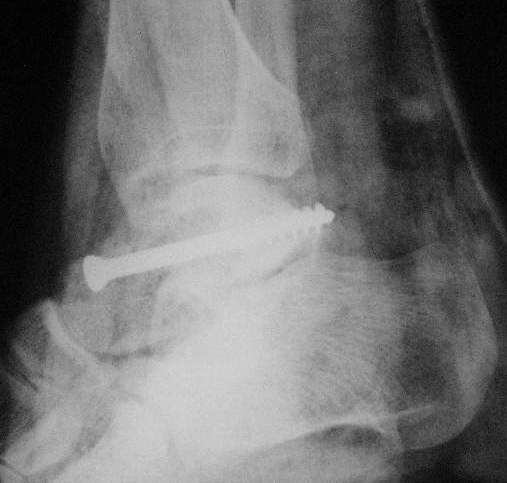

Прооперировали таранную кость, доступ внутренний без пересечения внутренней лодыжки. Хотя покаялись, что не пошли на остеотомию лодыжки внутренней. Винт

провели через небольшой передний доступ.